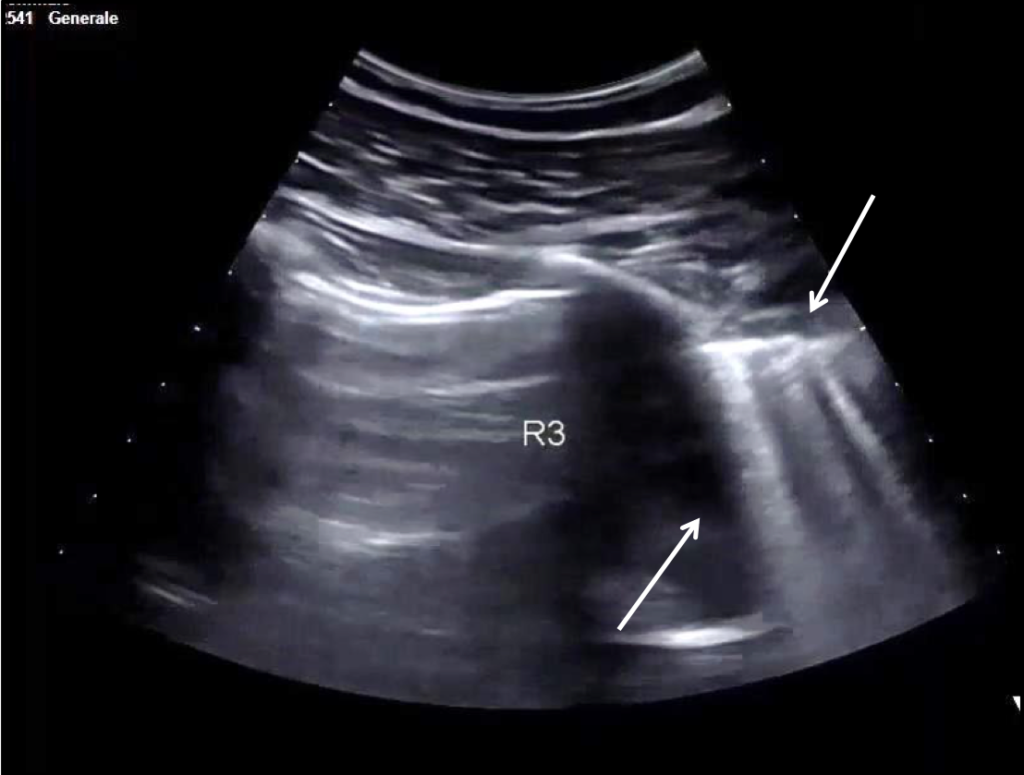

Video 1: Lung consolidation in the basal segment of the lower right lobe after patient deterioration (day 2).

A 30-year-old man presents to the emergency department (ED) due to syncope. For the last 10 days he had had fever, cough and dyspnea. At the ED his peripheral oxygen saturation was 86%, BP 130/80, HR 88bpm, RR 20 /min and his temperature 37.4°C. He was given oxygen via a mask. Chest CT was performed and later lung ultrasound (LUS) was performed in 12 areas longitudinal/oblique views using a convex array probe followed by a linear array probe for details (figure 1).

On imaging, initial lesions are usually peripheral because SARS-COV-2 attacks the small distal airways. Several reports have described the findings in chest CT. Most commonly few, small, segmental ground glass opacities are seen peripherally and basal. These may deteriorate to become bilateral and multisegmental and finally consolidation and/or ARDS. Most common LUS signs are: vertical pleurogenic artifacts with varying degree of intensity (from few to confluent). These alternate with clear demarcation to A-lines in the same area, especially in the mid- and upper lung. Pleural thickening, sometimes marked, due to the presence of numerous, small subpleural consolidations. Lobar or translobar consolidations of large size and minimal pleural effusions. The LUS features match with the site and kind on CT.